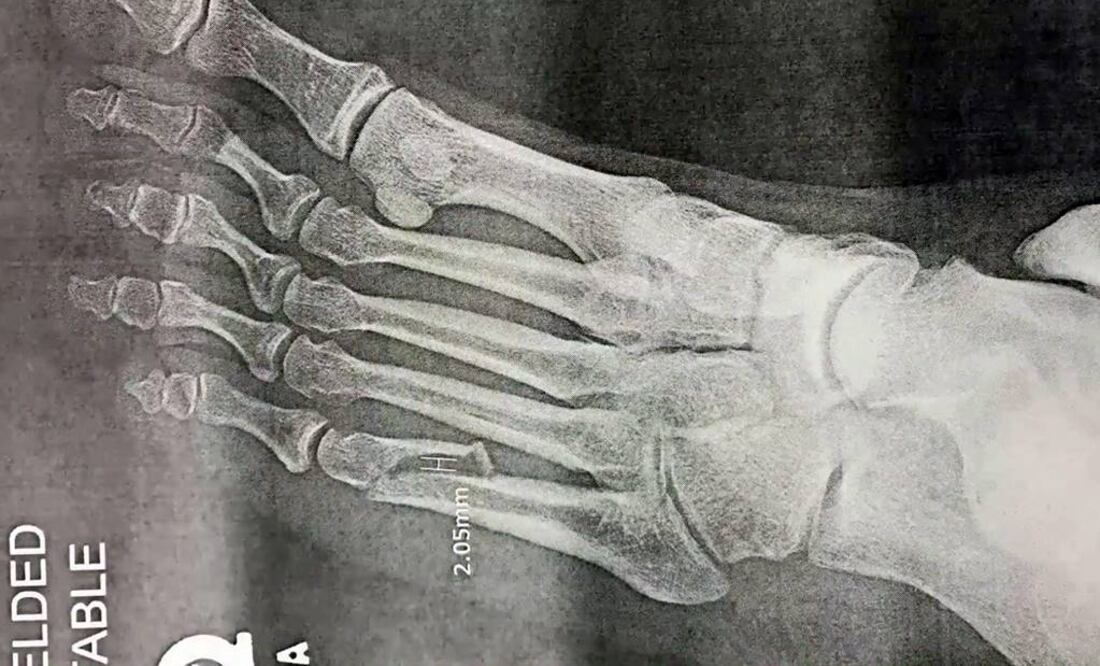

El cantante de la voz inconfundible anunció esta tarde que sufrió la fractura del quinto metatarso izquierdo y ya fue intervenido quirúrgicamente.

“Esto es lo que puede suceder cuando haces algo que no has hecho en casi 23 años”, tuiteó Rose esta tarde y compartió un video donde se observa a una especialista en traumatología explicando la radiografía de la lesión.

En el material se explica que el hueso del intérprete fue sometido a una reducción abierta y fijación interna, que consiste en colocar un fijador y tornillos (generalmente de titanio) para sujetar ambas partes del hueso de manera que queden alineadas y sanen sin necesidad de colocar un yeso.